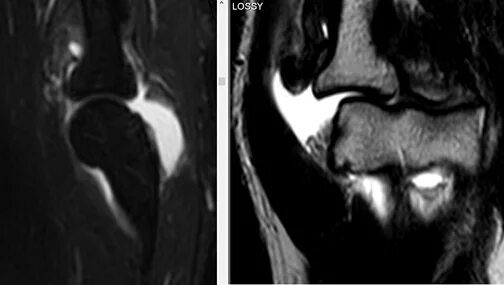

Что такое синовит коленного сустава на мрт